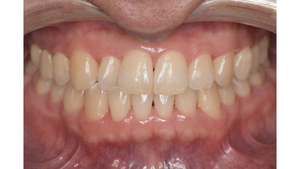

Before

症例

after

基本情報

年齢・性別 41歳・男性

主訴 主訴:歯ぐきから出血する

治療部位:全顎

治療内容 1.歯周ポケット検査、資料取り(レントゲン写真14枚・口腔内写真)、歯磨き指導

2.歯磨き指導チェック、縁上の歯石除去

3.縁下の歯石除去4回

4.再評価(歯周ポケット検査・レントゲン写真14枚・口腔内写真)

5.メインテナンス

治療期間 1日

治療費 合計:14,160円

内訳(全て保険診療3割負担)

・初診検査、歯磨き指導、縁上の歯石除去:3,630円

・レントゲン写真、縁下の歯石除去①:3,040円

・縁下の歯石除去②:1,530円

・歯磨き指導チェック、縁下の歯石除去③:2,070円

・縁下の歯石除去④:1,530円

・再評価:2,360円

(2022年5月現在現在)

リスク・副作用 ・歯石除去後すぐは歯ぐきを触っているため歯ぐきに違和感や痛みを感じる場合がある

・歯石除去により今まで腫れていた歯ぐきが引き締まり歯ぐきが下がる可能性がある

・歯ぐきが引き締まって下がることにより歯面が今までより露出し知覚過敏の症状がでる可能性がある

・歯石除去後、歯磨きを怠ると細菌が歯周ポケットのより深部まで入ってしまうため歯周病が悪化してしまう可能性がある

・一度歯周病になると再発しやすい為、定期的なメインテナンスが必要になります

治療方針 1.歯磨き指導

2.歯ぐき上の歯石除去

3.歯ぐき下の歯石除去

4.再評価

5.定期的なメインテナンス

特記事項 ・着色除去(PMTC)は自費治療のため希望しませんでした。

・右下7番の歯周ポケット5mmは親知らずの関係もあり、このまま維持していくことを説明しています。

・他4mmの歯周ポケットに関しては歯垢が少し残っていた為、再度歯磨き指導と、縁下の歯石を確認して様子をみることにしました。

担当者所見 全体的に出血が見られたのと、奥の歯ぐきは炎症があり歯周ポケットが深かった為、まずは歯ブラシの当て方+歯間ブラシ3Sサイズを使用して頂き炎症を落ち着かせました。

両方毎日使用して頂いた為、スムーズに歯周病治療を行うことができました。毎日のホームケアが不十分だと、なかなか結果に繋がらず、治療期間も長くかかってしまう為、患者様の協力が歯周病治療を成功させるためにはかなり重要になっていきます。

そして一度病気になった歯ぐきは再発しやすい為、今後は3ヶ月に1度の定期的なメインテナンスで、この状態を維持できるよう一緒に管理していきます。